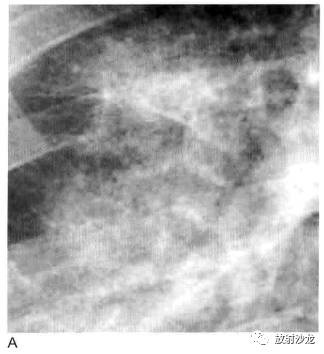

图1 实变:均匀致密影、纹理遮盖,空气支气管征和CT血管造影征 医学百科网 | YxBaike.Com

A. 肺水肿所致的右肺实变。可见双侧实变肺内 空气支气管征,肺血管模糊;B.右肺中下叶肺炎患者增强CT显示病变区均匀实变、肺体积保持不变,空气支气管征(黑色箭头)和致密学观影(白色箭头),其密度高于邻近实变肺组织(即“CT血管造影”征) 医学百科网 | YxBaike.Com